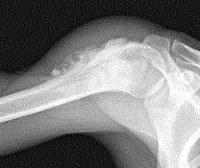

Опухоли костей. Группа злокачественных и доброкачественных новообразований, возникающих из костной либо хрящевой ткани. Чаще в эту группу относят первичные опухоли, но ряд исследователей называет опухолями костей и вторичные процессы, которые развиваются в костях при метастазировании злокачественных новообразований, расположенных в других органах. Для уточнения диагноза используется рентгенография, КТ, МРТ, УЗИ, радионуклидные методы и биопсия тканей. Лечение доброкачественных и первичных злокачественных опухолей костей обычно оперативное. При метастазах чаще используются консервативные методики.

Остеохондрома (другое название костно. Хрящевой экзостоз) - опухоль кости, которая локализуется в зоне хряща длинных трубчатых костей. Состоит из костной основы, покрытой хрящевым покровом. В 30% случаев остеохондрома выявляется в области колена. Может развиваться в проксимальной части плечевой кости, головке малоберцовой кости, позвоночнике и костях таза. Из-за расположения вблизи сустава нередко становится причиной реактивного артрита, нарушения функции конечности. При проведении рентгенографии выявляется четко очерченная бугристая опухоль с негомогенной структурой на широкой ножке. Лечение - резекция, при образовании значительного дефекта - костная пластика. При множественных экзостозах ведется динамическое наблюдение, операция показана при быстром росте или сдавлении соседних анатомических образований. Прогноз благоприятный.

Остеогенная саркома. Опухоль кости, возникающая из костной ткани, склонная к бурному течению, быстрому образованию метастазов. Развивается преимущественно в возрасте 10-30 лет, мужчины страдают вдвое чаще женщин. Обычно локализуется в метаэпифизах костей нижних конечностей, в 50% случаев поражает бедро, затем следуют большеберцовая, малоберцовая, плечевая, локтевая кости, кости плечевого пояса и таза. На начальных стадиях проявляется тупыми неясными болями. Затем метаэпифизарный конец кости утолщается, ткани становятся пастозными, образуется видимая венозная сеть, формируются контрактуры, боли усиливаются, становятся невыносимыми.На рентгенограммах бедра, голени и других пораженных костей на начальных стадиях выявляется очаг остеопороза со смазанными контурами. В последующем образуется дефект костной ткани, определяется веретенообразное вздутие надкостницы и игольчатый периостит. Лечение - оперативное удаление опухоли. Раньше применяли ампутации и экзартикуляции, теперь чаще выполняют органосохраняющие операции на фоне пред- и послеоперационной химиотерапии. Дефект кости замещают аллопротезом, имплантатом из металла или пластика. Пятилетняя выживаемость - примерно 70% при локализованных опухолях.

На рентгенограммах бедра, голени и других пораженных костей на начальных стадиях выявляется очаг остеопороза со смазанными контурами. В последующем образуется дефект костной ткани, определяется веретенообразное вздутие надкостницы и игольчатый периостит. Лечение - оперативное удаление опухоли. Раньше применяли ампутации и экзартикуляции, теперь чаще выполняют органосохраняющие операции на фоне пред- и послеоперационной химиотерапии. Дефект кости замещают аллопротезом, имплантатом из металла или пластика. Пятилетняя выживаемость - примерно 70% при локализованных опухолях.